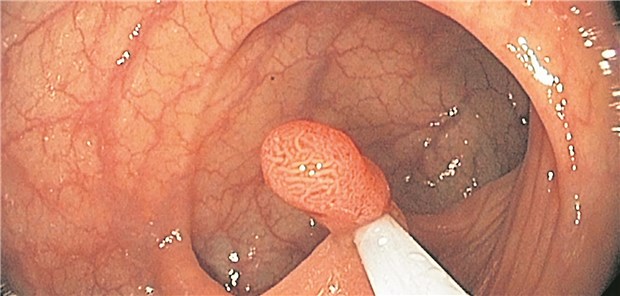

Ein Adenom wird abgetragen: Die Inzidenzrate für ein kolorektales Karzinom betrug bei Patienten mit fortgeschrittenen Adenomen 20 pro 10000 Personenjahre.

© Albertinen KH / endoskopiebilder

Koloskopie

Fortgeschrittene Adenome – erhöhte Darmkrebsinzidenz